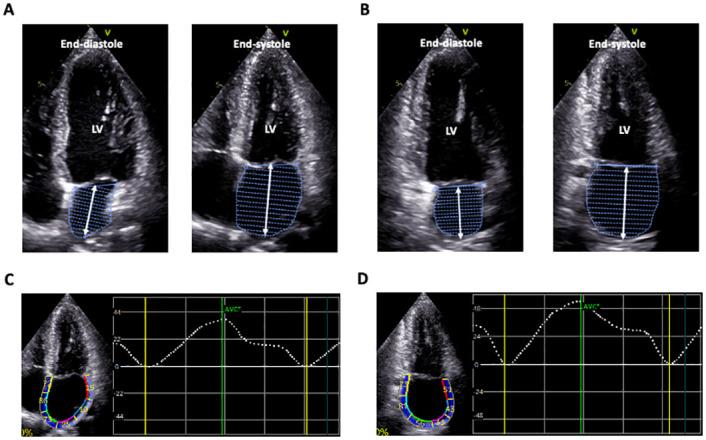

Standard apical four-chamber and two-chamber views often maximize the long-axis of the left ventricle, resulting in artifactitious foreshortening of the left atrium (LA), which may overestimate LA longitudinal reservoir strain (LALS). We compared LALS values between 2D echocardiography (2DE) and 3D echocardiography (3DE) in healthy subjects to determine whether 2DE speckle tracking analysis overestimates the reference value of LALS.

In this study, 4 types of cohorts were included: 1. 105 normal subjects (retrospectively), 2. 53 patients with cardiovascular diseases (retrospectively), 3. 15 patients who received cardiac magnetic resonance (prospectively), and 4. 20 normal subjects (prospectively). LALS and LA length were measured using both 2DE and 3DE in 105 healthy subjects (median age: 42 years). Biplane LALS was measured in apical four- and two-chamber views using 2DE speckle tracking software, and 3DE LALS was measured using new 3DE LA strain software. To determine sensitivity, we also performed the same analysis in 53 patients with cardiovascular disease. The mean value of biplane LALS was 39.6%. LA length at both end-diastole (r = -0.43) and end-systole (r = -0.54) was negatively correlated with biplane LALS. Multivariate regression analysis revealed that both end-diastolic and end-systolic LA length had significant negative relationships with biplane LALS after adjusting for anthropometric and echocardiographic image quality parameters. 3DE LALS (23.7±7.6%) gave significantly lower values than 2DE LALS (39.5±12.0%, p<0.001) with a weak correlation (r = 0.33). LA length measured by 2DE was significantly shorter than that measured by 3DE. The same trend was observed in diseased patients.

标准的心尖四腔心和两腔心切面通常可使左心室长轴最大化,从而导致左心房(LA)的人为缩短,这可能会高估左心房纵向储备应变(LALS)。我们比较了健康受试者中二维超声心动图(2DE)和三维超声心动图(3DE)的 LALS 值,以确定 2DE 斑点追踪分析是否高估了 LALS 的参考值。

本研究纳入了 4 种队列:1. 105 名正常受试者(回顾性);2. 53 名心血管疾病患者(回顾性);3. 15 名接受心脏磁共振检查的患者(前瞻性);4. 20 名正常受试者(前瞻性)。在 105 名健康受试者(中位年龄:42 岁)中,使用 2DE 和 3DE 分别测量 LALS 和左心房长度。使用 2DE 斑点追踪软件在心尖四腔心和两腔心切面测量双平面 LALS,使用新的 3DE LA 应变软件测量 3DE LALS。为了确定敏感性,我们还对 53 名心血管疾病患者进行了相同的分析。双平面 LALS 的平均值为 39.6%。舒张末期(r = -0.43)和收缩末期(r = -0.54)的左心房长度与双平面 LALS 呈负相关。多变量回归分析显示,在调整了人体测量和超声心动图图像质量参数后,舒张末期和收缩末期左心房长度与双平面 LALS 均呈显著负相关。3DE LALS(23.7±7.6%)明显低于 2DE LALS(39.5±12.0%,p<0.001),两者相关性较弱(r = 0.33)。2DE 测量的左心房长度明显短于 3DE 测量的长度。在患病患者中也观察到了相同的趋势。